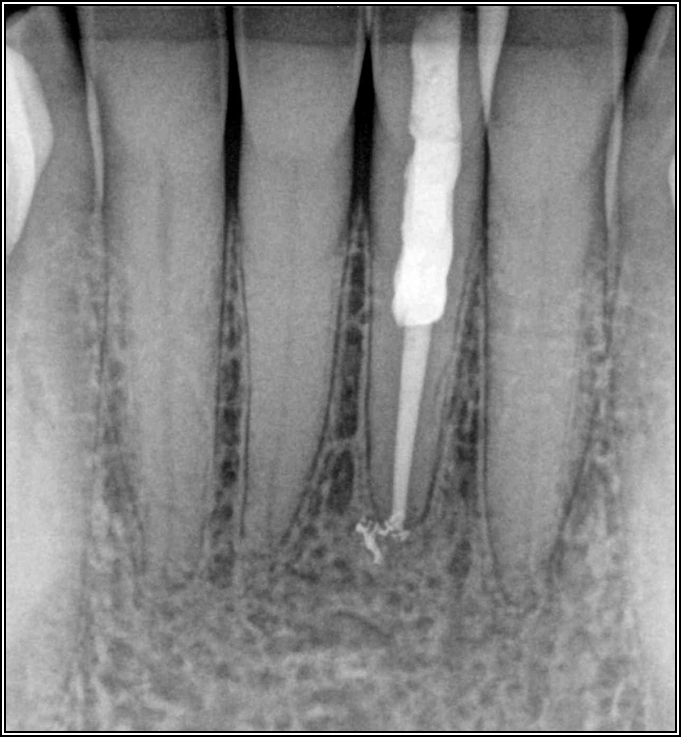

Figure 2 shows a situation where the clinician excavated the tooth of a patient with decay, and it pulped out. The buccal and lingual walls were intact; however, the walls were minimal, and there were still fragments of amalgam and cracks. If the clinician prepared this tooth after building it up, the clinician would lose all the good tooth structure that was left. This tooth would likely need a post.

Fig 2. Minimal walls.

Figure 2